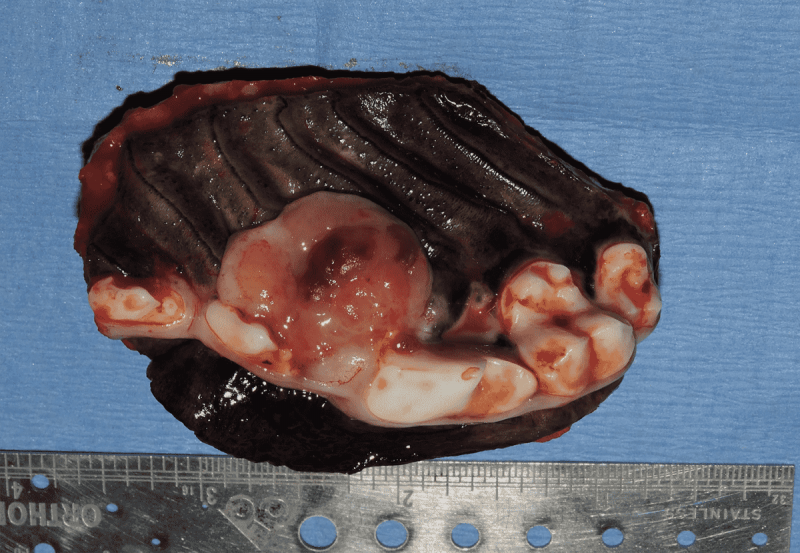

Tumors of the Maxilla, Mandible and Facial Area

Oral tumors are very common in dogs and cats. Many of these tumors can be successfully removed with surgery. Benign tumors can be cured with surgery alone, and malignant tumors can be treated with surgery and some combination of radiation or chemotherapy. In many cases oral tumors cause a great degree of discomfort or are bleeding and need to be removed to allow your pet to be more comfortable.